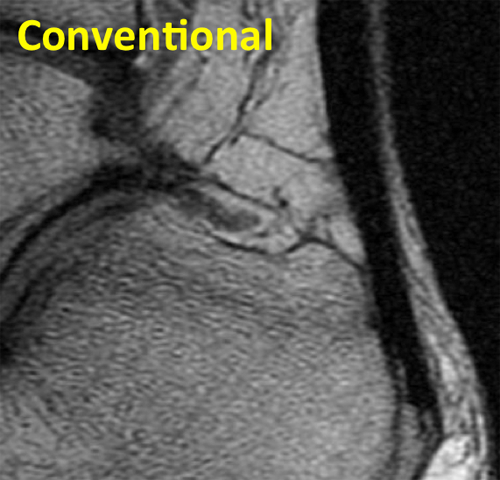

Tendon Conventional

Conventional sagittal MR image of the ankle shows the low signal intensity Achilles tendon.